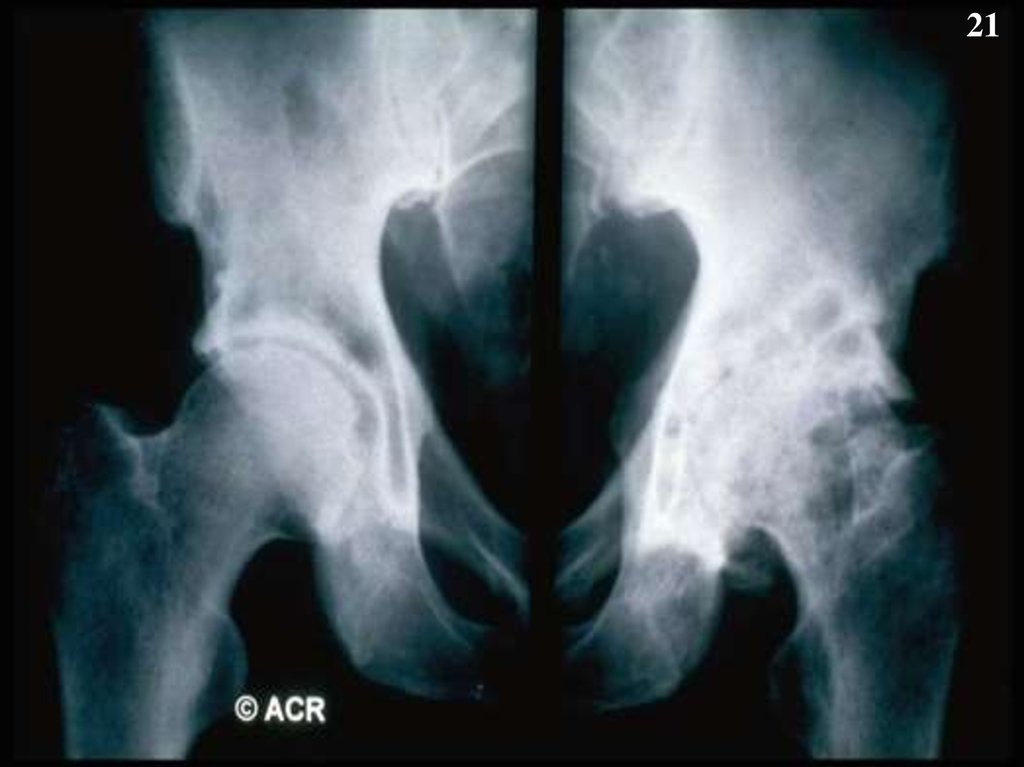

21.

21